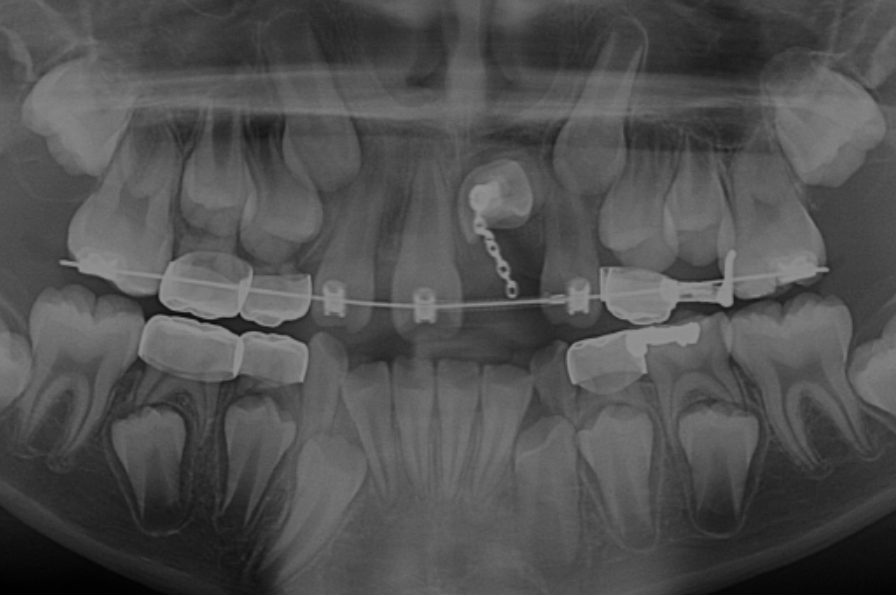

Ectopic Eruption

Ectopically erupting maxillary molar